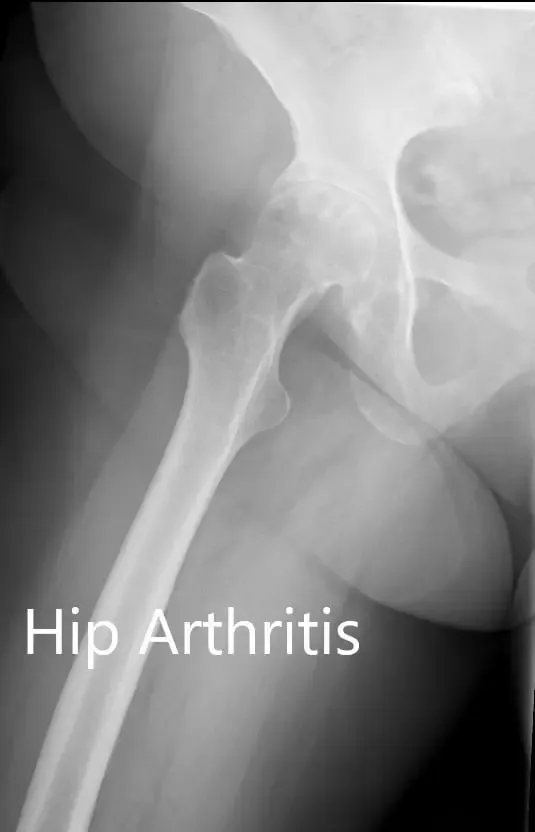

No había déficit neurológico distal. Los pulsos distales en las extremidades tenían buen volumen y eran palpables. Había una cicatriz lineal sobre la rodilla derecha consistente con una prótesis anterior de la rodilla derecha. Los estudios de imagen revelaron una osteoartritis severa en la cadera derecha.

Radiografía preoperatoria que muestra la vista AP de la pelvis con ambas articulaciones de la cadera

Radiografía preoperatoria que muestra la visión de la pata de rana y la pata lateral de la cadera derecha